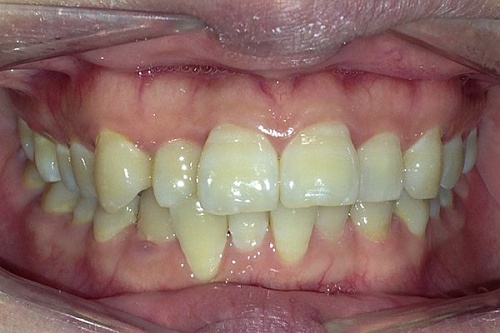

Изменения тканей, которые окружают корни зубов, к сожалению, неизбежны и с возрастом наблюдаются у всех, однако в разном объеме. Так, на развитие пародонтита влияет болезнетворная микрофлора полости рта, которая есть у каждого из нас, но на мы в силах повлиять на ее количество.

Сохранить зубы и пародонт помогает правильная гигиена полости рта дома и в кресле стоматолога, а также своевременное протезирование и имплантация, которые замещают удаленные зубы и равномерно распределяют жевательную нагрузку, не позволяя костной ткани атрофироваться.